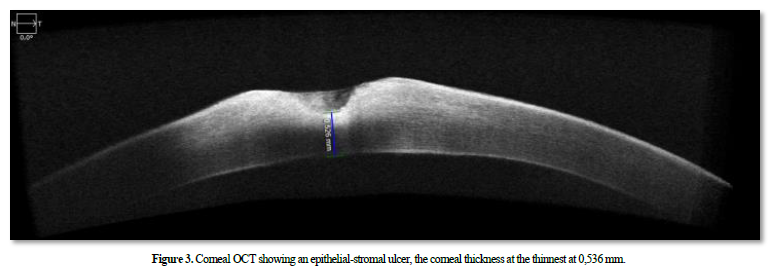

Fundus examination appeared normal. The examination of the right eye was unremarkable. The anterior segment optical coherence tomography (OCT) revealed an epithelial-stromal ulcer, the corneal thickness at the thinnest at 0,536 mm (Figures 3).